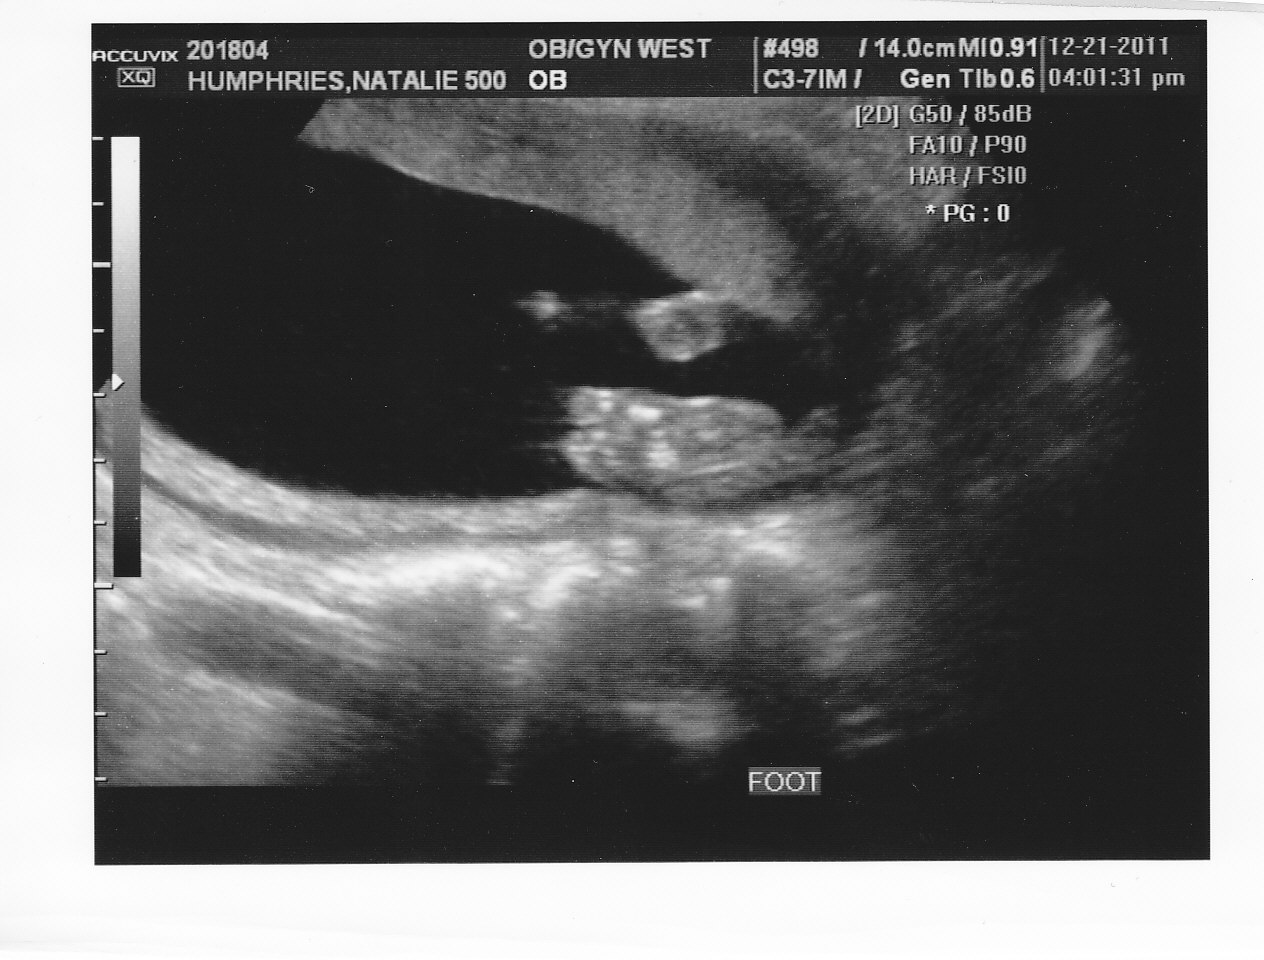

So it looks like Brad and Maddie are going to have a little sister this Spring!! We went in for our 21 week ultrasound this week and were thrilled with all of the results.  We have a healthy little girl growing and developing just as she should be.  :) Our due date was right on, so we are still looking at May 3rd 2012 for the arrival of our newest family member.  We are very excited that Maddie and her sister will be so close in age and be able to have such a special relationship growing up.  If this one comes early like Maddie did, they will technically be "Irish Twins".  Brad will have his work cut out watching out for two little sisters, but he sounds very excited and up for the challenge.  Here are a few of the ultrasound pictures that we were able to take home.

The ultrasound tech had NO DOUBT she was a little girl.  :)